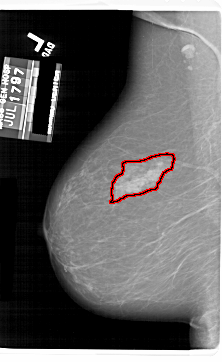

A_1802_1.LEFT_CC

LEFT_CC LINES 5956 PIXELS_PER_LINE 3901 BITS_PER_PIXEL 12 RESOLUTION 43.5 OVERLAY

FILE: A_1802_1.LEFT_CC.OVERLAY

TOTAL_ABNORMALITIES 1

ABNORMALITY 1

LESION_TYPE MASS SHAPE ASYMMETRIC_BREAST_TISSUE MARGINS ILL_DEFINED

ASSESSMENT 4

SUBTLETY 5

PATHOLOGY BENIGN

TOTAL_OUTLINES 1

BOUNDARY